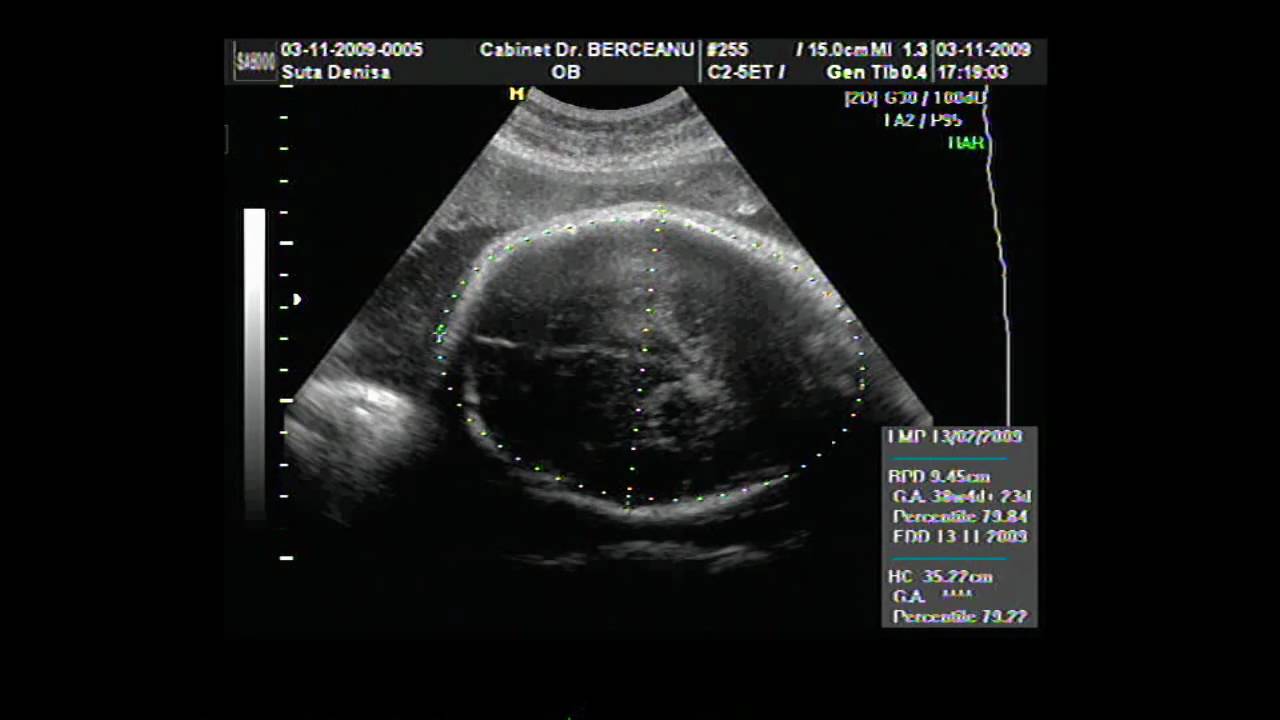

Размеры плода или фетометрия должны быть приближены к таким показателям:

- Окружность живота равняется 304-368 миллиметров

- Окружность головы составляет от 309-357 мм

- Лобно-затылочный размер от 108 до 128 миллиметров

- Бипариетальный параметр составляет 86 – 100 мм